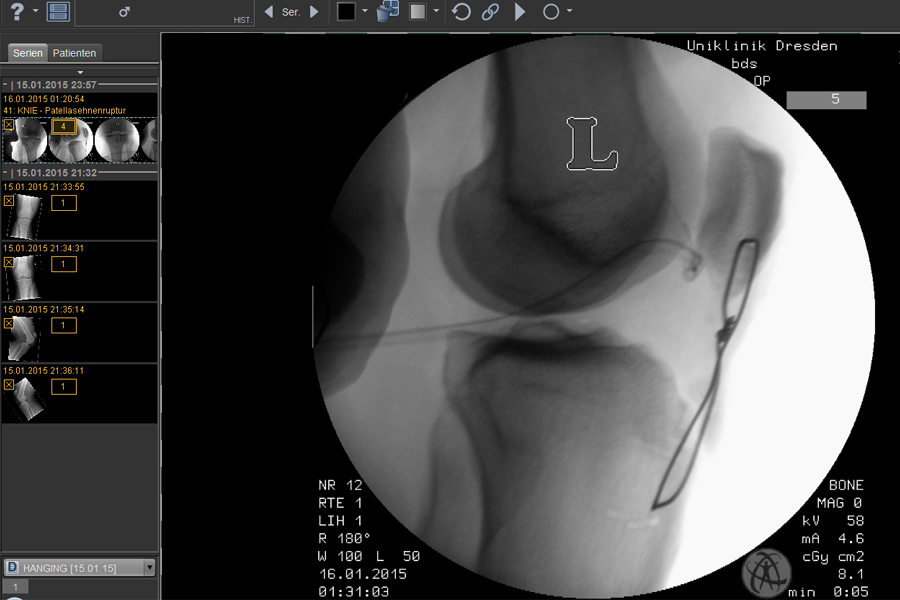

Das "Erlebnis" einer beidseitigen Patellasehnenruptur